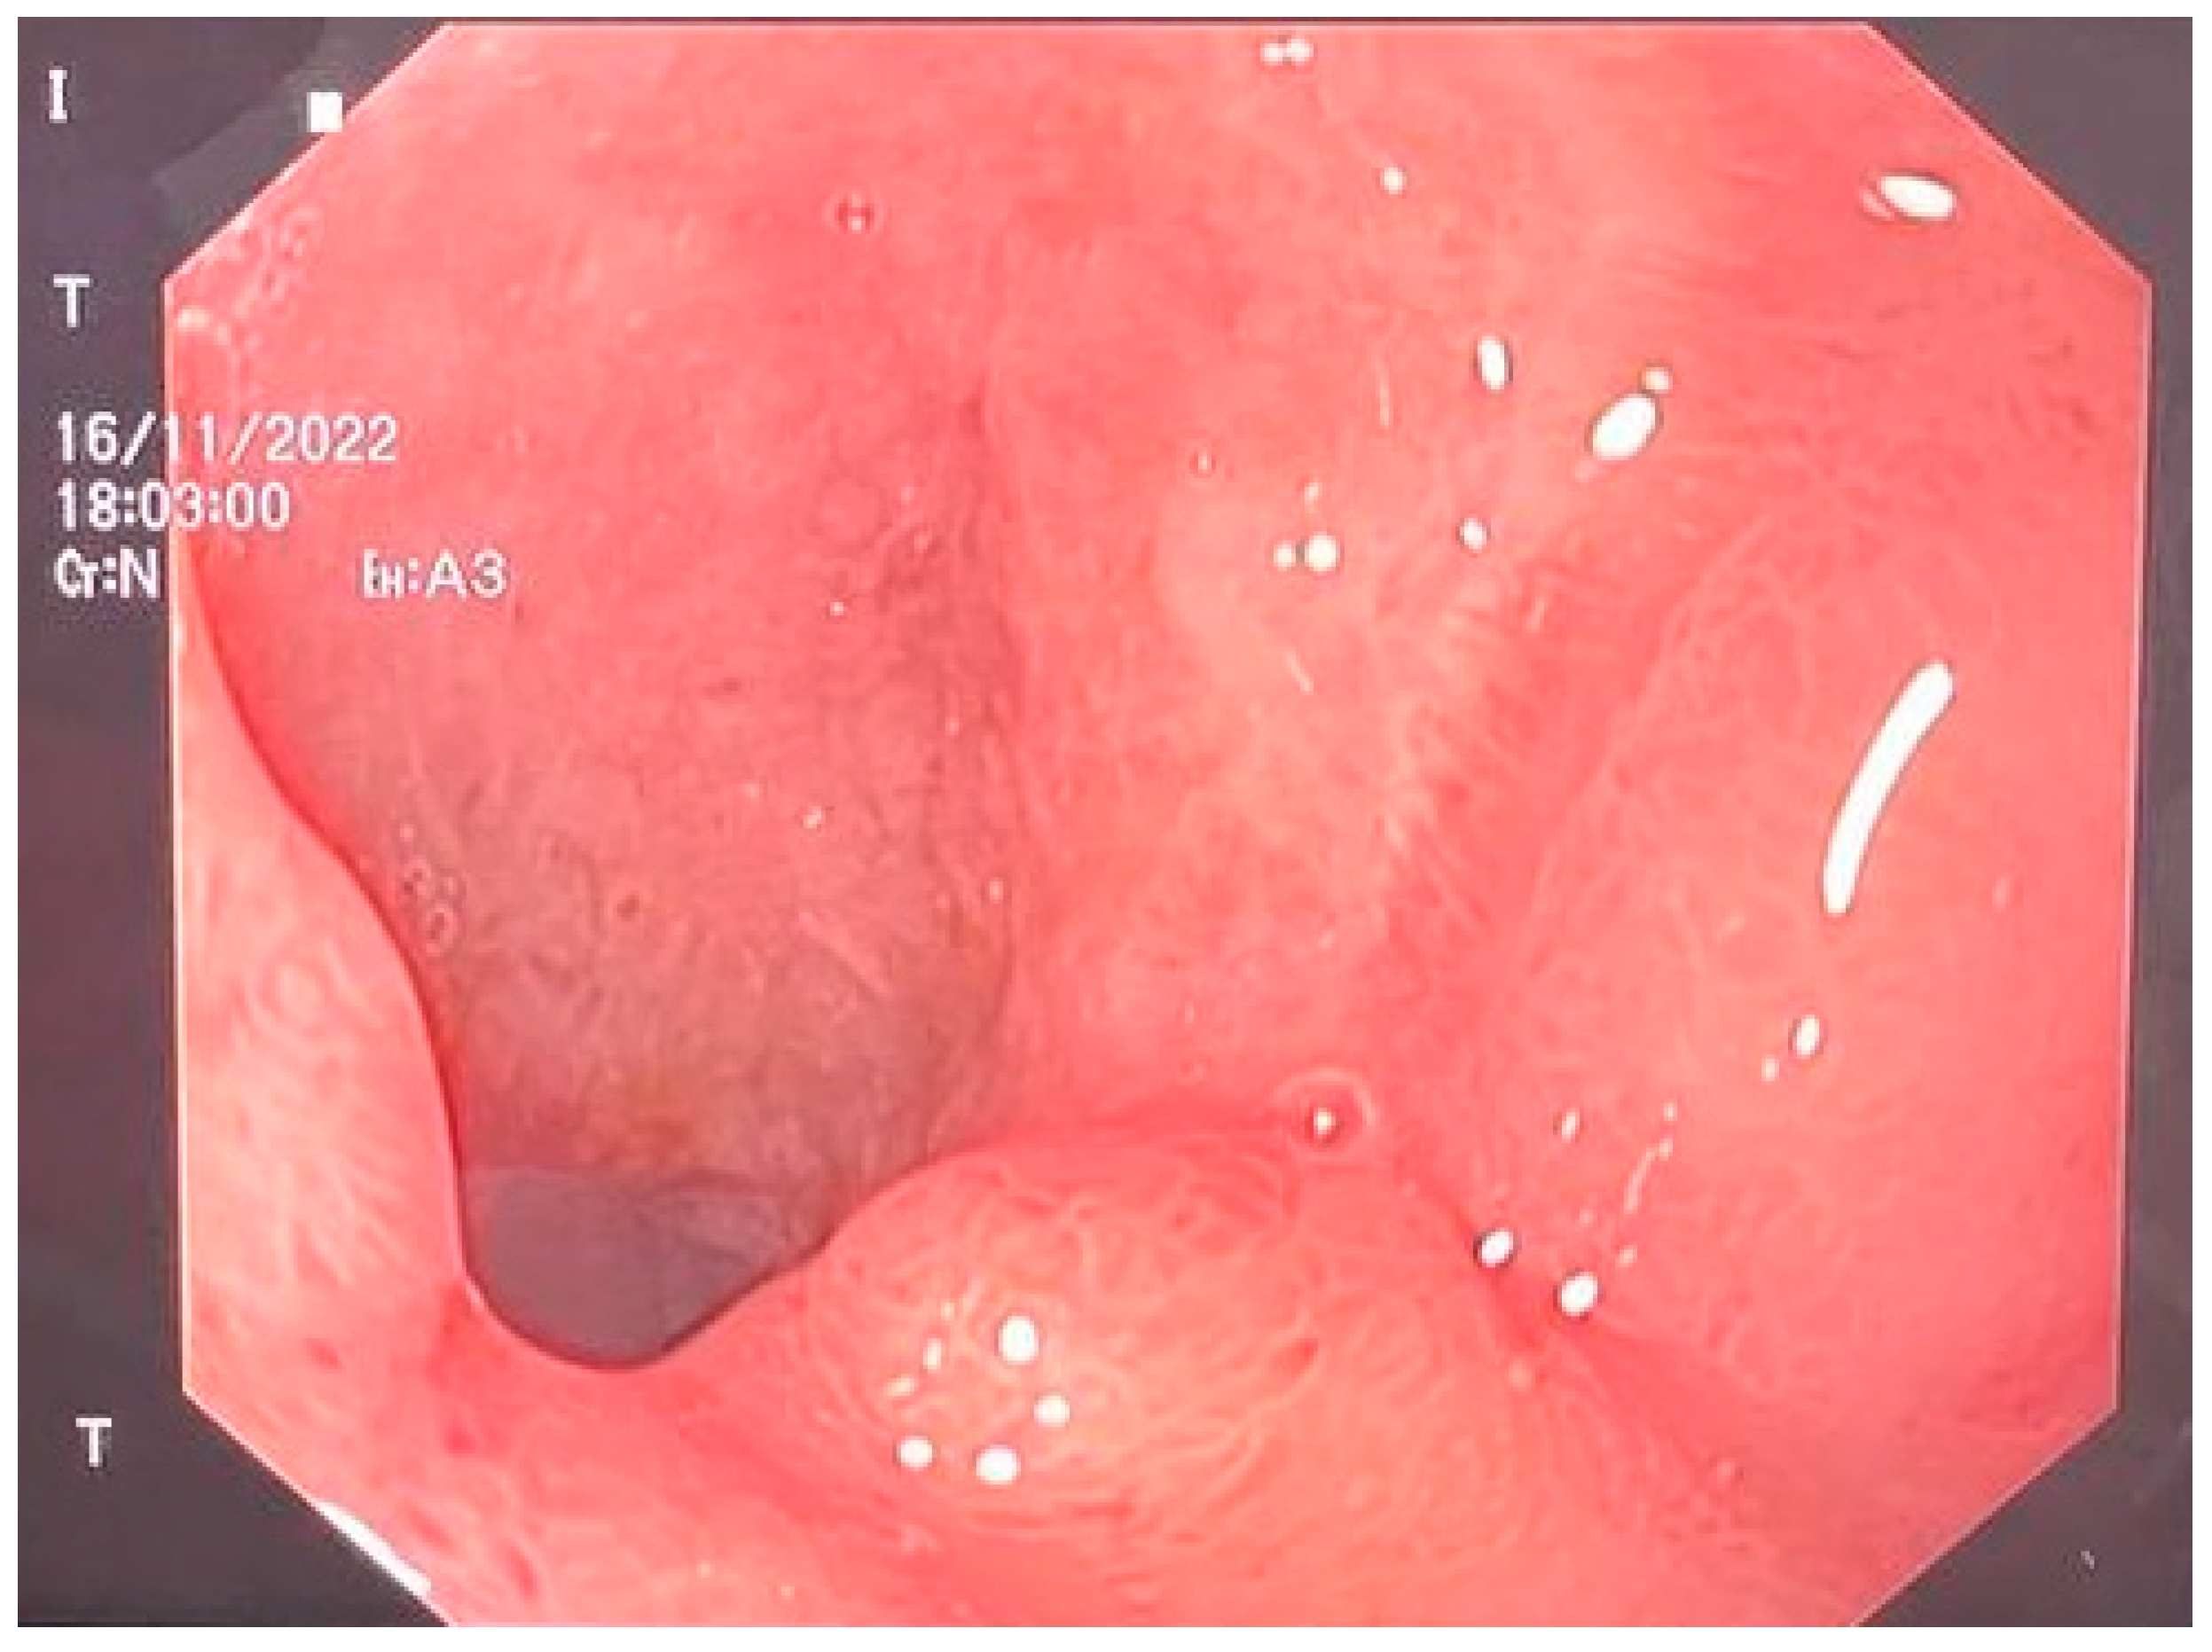

We decided to use E-VAC. We prepared the required materials as follows: a double-lumen nasogastric tube, an S-sized vacuum kit, small surgery instruments, and a vacuum pump. The sponge was prepared and adjusted to the dimensions of the cavity in question according to the measured dimensions. The nasogastric probe was prepared according to the length of the sponge, with attention placed on the location of the openings through which the secretions would be aspired. The openings were located within the proximal and distal edges of the sponge sleeve. The path of the nasogastric probe was cut in the sponge following an imaginary line through the center along the entire length (Figure 2a,b) (patent number: RO135252). The model of the probe allowed the local instillation of substances such as antibiotics and, at the same time, washing and controlling the tightness of the cavity where it was placed.

Figure 2.

(a) E-VAC aspect of the distal end; (b) E-VAC device ready for installation.